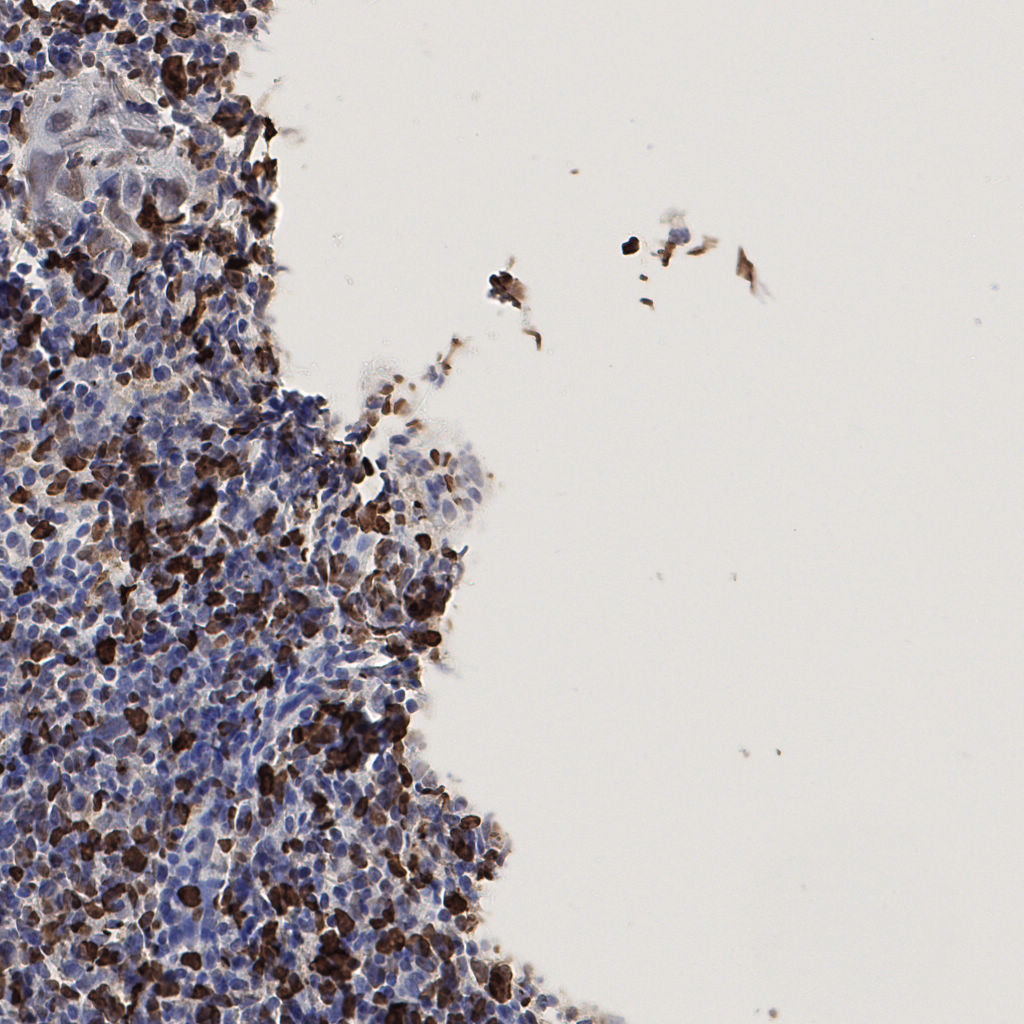

7.85%

Ki67 指数

阴 1104 阳 94